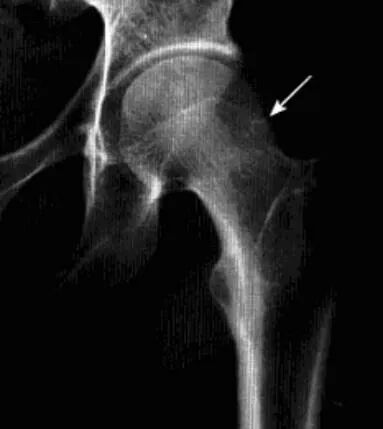

血友病性髋关节炎

血友病患者关节内反复出血所致关节退行性病变,好发于活动多和承受重力的关节,*常累及膝、肘、踝关节,髋关节较少。

病理:关节内出血刺激滑膜炎症反应、增生、绒毛形成,关节囊及滑膜增厚、纤维化,软骨下出血可致软骨坏死脱落,骨质增生、囊变,关节畸形或纤维强直,儿童骨骺增大、骺板提前闭合。

临床表现:男性,儿童多见,关节肿胀,肌肉萎缩,多脏器出血症状,实验室凝血异常。

影像诊断:X线平片典型改变可确诊,CT及MRI可清晰显示软骨及腔内改变。

1、平片:早期髋关节间隙增宽,关节囊肿胀,软组织密度增高,骨性关节面光。中后期出现骨侵蚀,关节间隙狭窄或消失,软骨下骨板致密,边缘骨赘形成及囊变,儿童骨骺增大、骺板提前闭合。

2、CT:髋关节腔内高密度或钙化,关节囊增厚,软骨下骨质小圆形和不规则软组织密度区,伴周围硬化缘,正常骨纹理消失,骨端骨质疏松。长期者呈骨性关节炎改变。

3、MRI:髋关节腔内出血为特征表现,滑膜及关节囊明显增厚,增强有明显强化;晚期关节面下硬化性病灶,骨质囊变,软骨坏死,纤维组织增生,陈旧性出血改变。